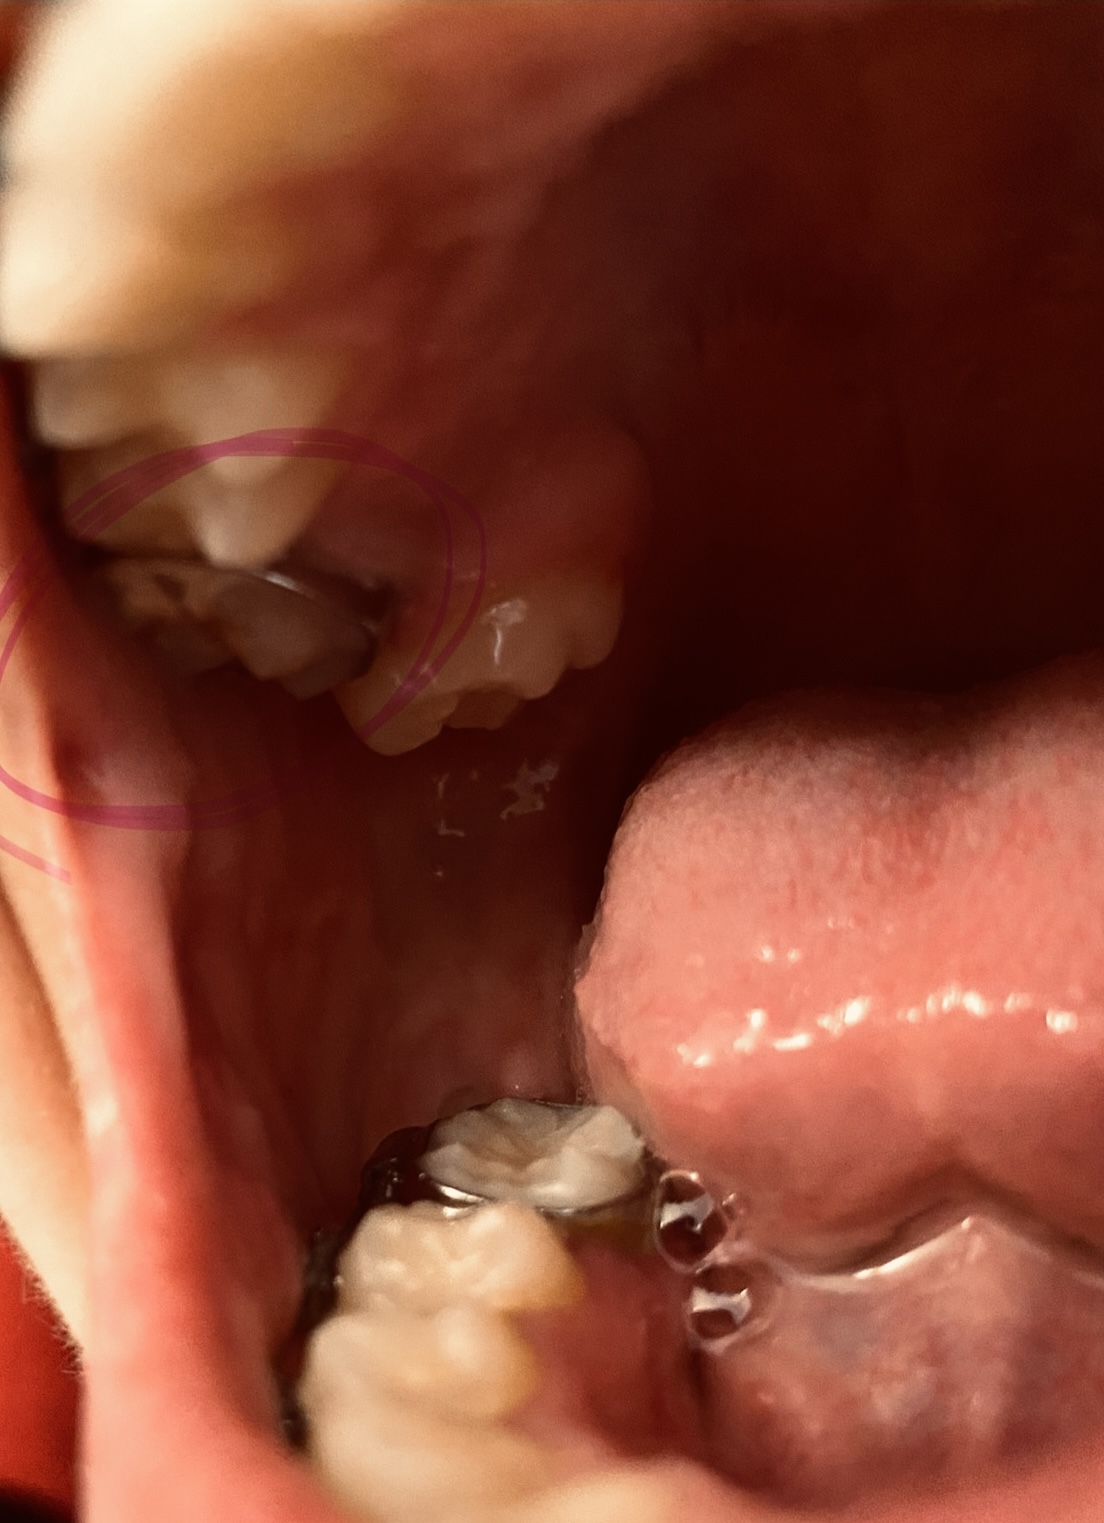

Almost-brodie bite with SFOT. Looking for provider recommendations

I went to my original orthodontist really wanting a wider smile and a fix to my overbite {content removed} sleep apnea. He proposed removing two premolars in order to prepare for double jaw surgery. I had the two lower premolars removed in addition...

Extraction During Braces for Scissor Bite Molar

Hello, i have a simple question regarding braces, over crowding etc. im a 15 year old girl with braces that have been on for 2 years, i have a scissor bite due to a severe crowding case and i have big teeth, i also have an overbite but its not too...